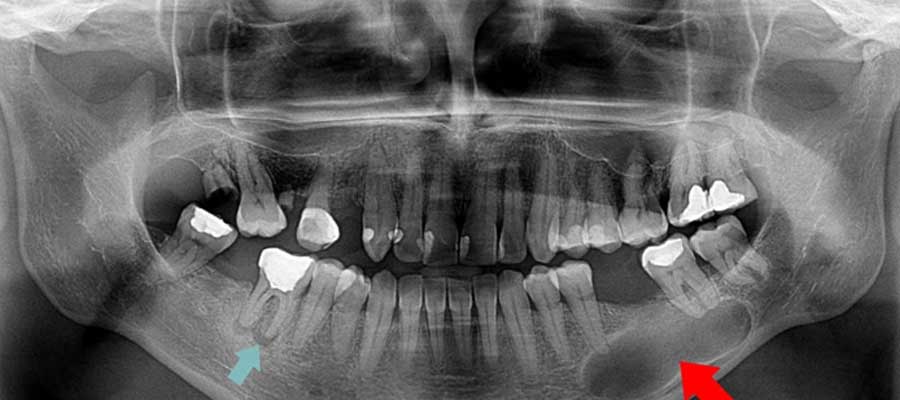

کیست دندان در عکس رادیولوژی

کیست دندان در عکس رادیولوژی معمولاً بهصورت یک ناحیه تیره (رادیولوسنت)، با حاشیه نسبتاً مشخص در اطراف ریشه دندان مشاهده میشود. تشخیص نهایی همیشه با نظر دندانپزشک و گاهی پاتولوژی انجام میشود.

| ظاهر در رادیولوژی | مرزهای مشخص و دایرهای | مرزهای نامنظم و تهاجمی |